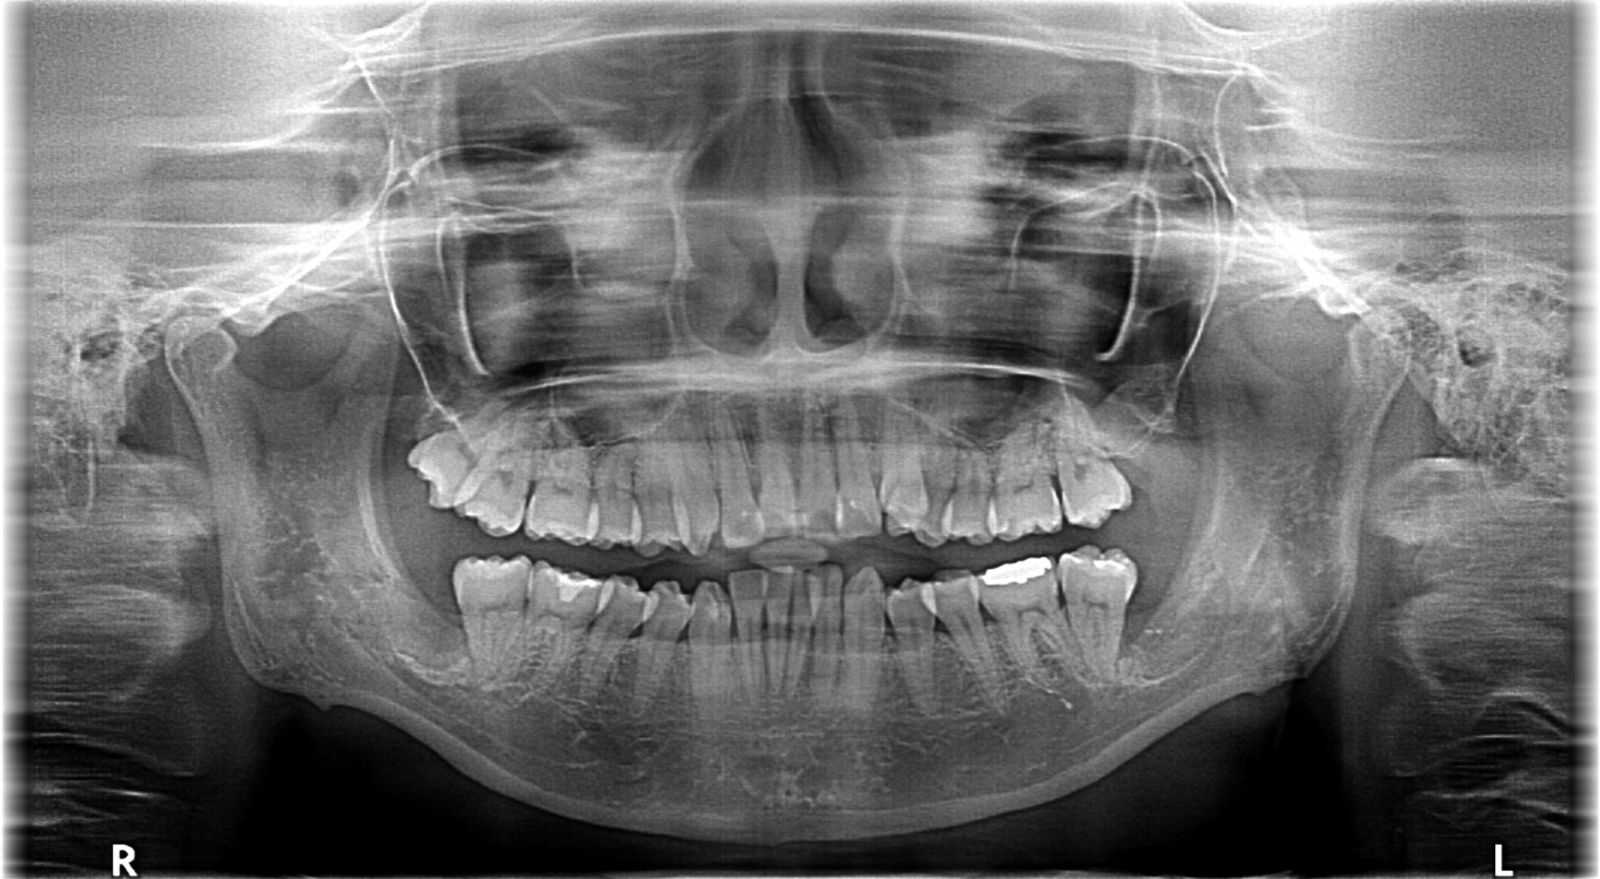

「CT」による診察・診断

CTは一般的なレントゲンとは異なり、顎の骨の厚さや神経までをも確認できます。そのため、埋伏歯など対応の難しい症例でも事前に精密に分析も可能になり、余分な切開や骨の切削などを避けることができ、治療の安全性・精度を大きく向上させることができます。